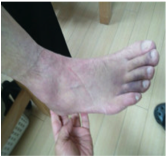

ふくろうおばさん 様 59才 ①どのような症状(痛みや悩み)で来院されましたか? 私は50代に入ってから、日々の健康の為に軽いジョギングを楽しんでいました。1年ほど前に戸外の石の階段の段差で左足首を強く捻りスジを痛めました。若いころから何度となく同じところを捻っていましたが、いつも日にち薬だとか、しばらく安静にするとかだけで治療せずに放置していました。ところが今年の冬のある日特に捻ってもいないのに運動後、痛みと共に足首がぐらぐらし歩くのも不安定な状態になりました。足首に体重をかけられず階段の昇り降りも怖くて困りました。「このまま歩けなくなったらどうしよう…」と不安になり、お世話になっているジョギングクラブのコーチに紹介され来院しました。 ②施術(治療)を受けられて症状(痛みや悩み)に変化はありましたか? 左足甲の靭帯を損傷しているという診断で、先生により手技治療を受けました。又回復を早める為に必要な種々の電気治療を受けながら、適切なリハビリ(運動療法)もマンツーマンで指導していただきました。日常的にはテーピングやサポーターで患部をしっかり固定しながら、定期的に通院しました。2ケ月経過した現在、ずいぶんと足首も安定し、ほとんど歩くことも気にならなくなりました。 傷めた部分をただ怖がって何もしないのではなく、その周辺の筋肉を刺激してバランスを整えることによって、不調な関節がだんだんと安定してくることが理解できました。そして諦めずに根気よく治療に通うことがとても大切であると痛感しました。先生からも「もう大丈夫ですよ」とのことばを頂き、勇気を出して無理のない範囲でまた少しずつ走ってみたいなと思えるようになりました。 |

| 足首の捻挫グセ→足関節不安定症→足根洞症候群の良くないパターンです。 足首の捻挫を甘く見ないでいただきたい。足元がグラつけば先々は足だけではなく全身に不安定の影響が出ることがあります。 治療もリハビリも基本通りにちゃんとやくだけです。やった分だけ結果が出ます。ふくろうおばさんはトレーニングの意味をちゃんと理解して続けられたことが良い変化につながりました。また、ウォーク、ランニング楽しんでください。 |